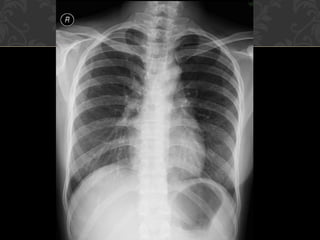

Paru

0 Kontusio paru

0 Cedera paling sering pada parenkim paru bila terjadi trauma

thoraks dengan prevalensi 17%–70%

0 Kontusio  cedera alveoli tanpa disrupsi

0 Muncul ketika terjadi trauma dan berada di lokasi trauma,

countercoup masih mungkin terjadi

0 Radiografi polos bisa mendiagnosis namun CT scan memiliki

sensitivitas lebih tinggi.

0 Radiografi  sekitar 6 jam

0 CT scan segera setelah trauma

0 Resolusi kontusio terjadi dalam waktu 1-2 hari dan hilang

sempurna dalam waktu 3-10 hari

0 Bila muncul area fokal lebih dari 24 jam  bukan kontusio